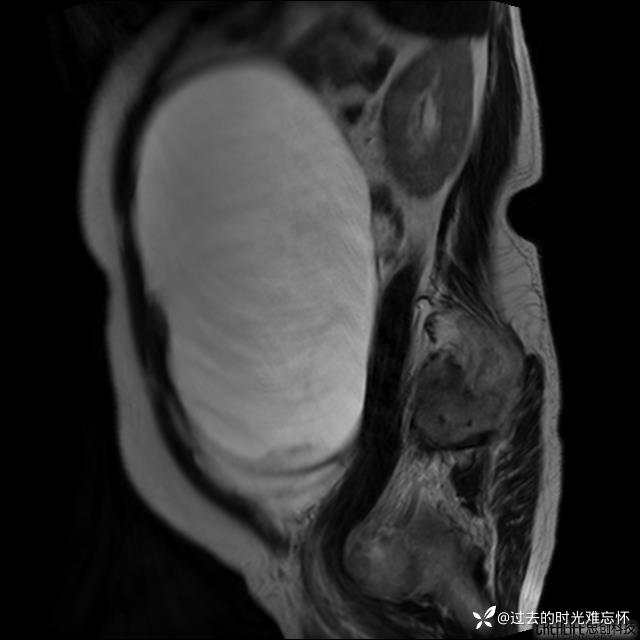

患者性别:女

患者年龄:65岁

主诉: 发现腹部隆起半年余。无其他明显不适。

浆液性囊腺瘤 (22)